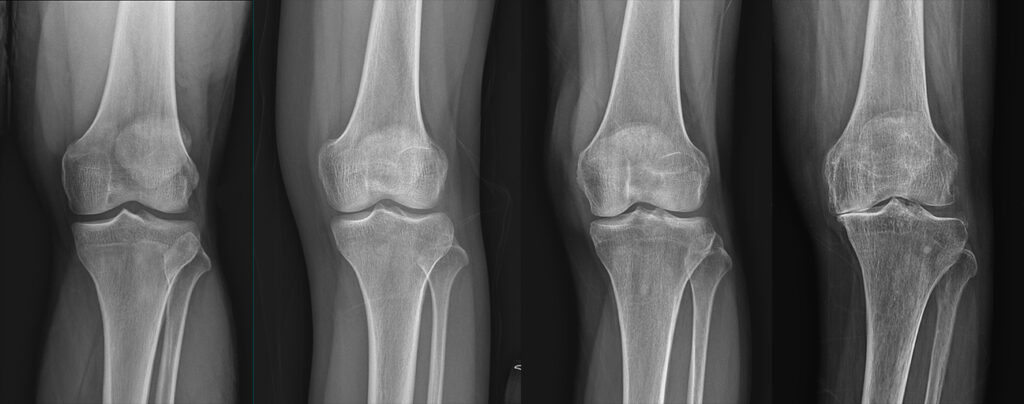

퇴행성 관절염은 나이가 들면서 자연스럽게 발생하는 관절의 마모로 인해 많은 사람들이 고통을 겪고 있는 질환입니다. 통증과 불편함 때문에 일상 생활에 큰 지장을 주기도 합니다.

심한 경우에는 약물 치료나 수술이 필요할 수 있습니다. 비스테로이드 항염증제(NSAIDs)는 통증과 염증을 줄이는 데 효과적이며, 경우에 따라 스테로이드 주사를 고려할 수 있습니다. 마지막으로, 관절이 심하게 손상된 경우 관절 치환술 같은 수술적 방법이 필요할 수 있습니다. 이러한 방법은 의사와 상담하여 결정하는 것이 중요합니다.